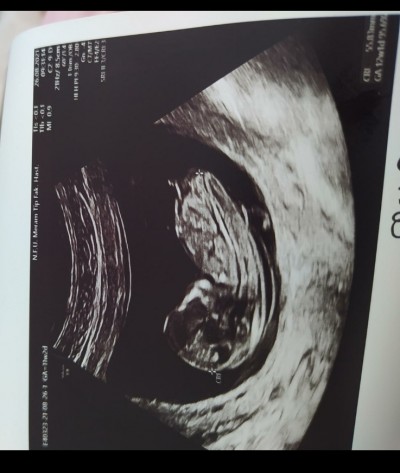

Merhaba kızlar ultrason fotoğrafına ya da Nub a göre cinsiyet tahmini yapabilir misiniz. Tecrübeli anneler merakla bekliyorum :)

Gebelik haftası 12 haftalık

Bebegin nubu kapali bu resimlerden birsey söylemek imkansiz

nubu goruyor musun acisina bak duz, dik degil